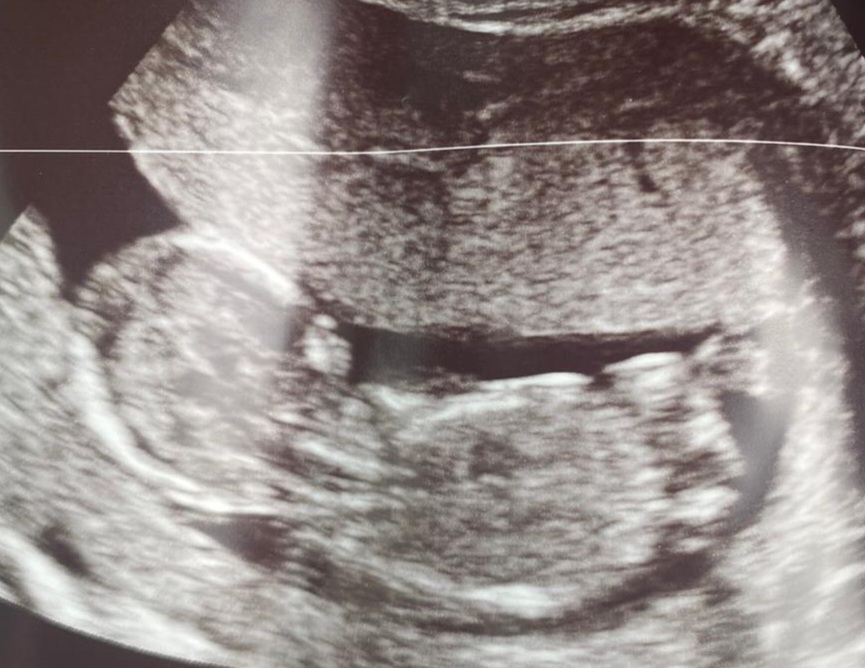

Nub guess ?

Attachment 43776

What is the gestation here?